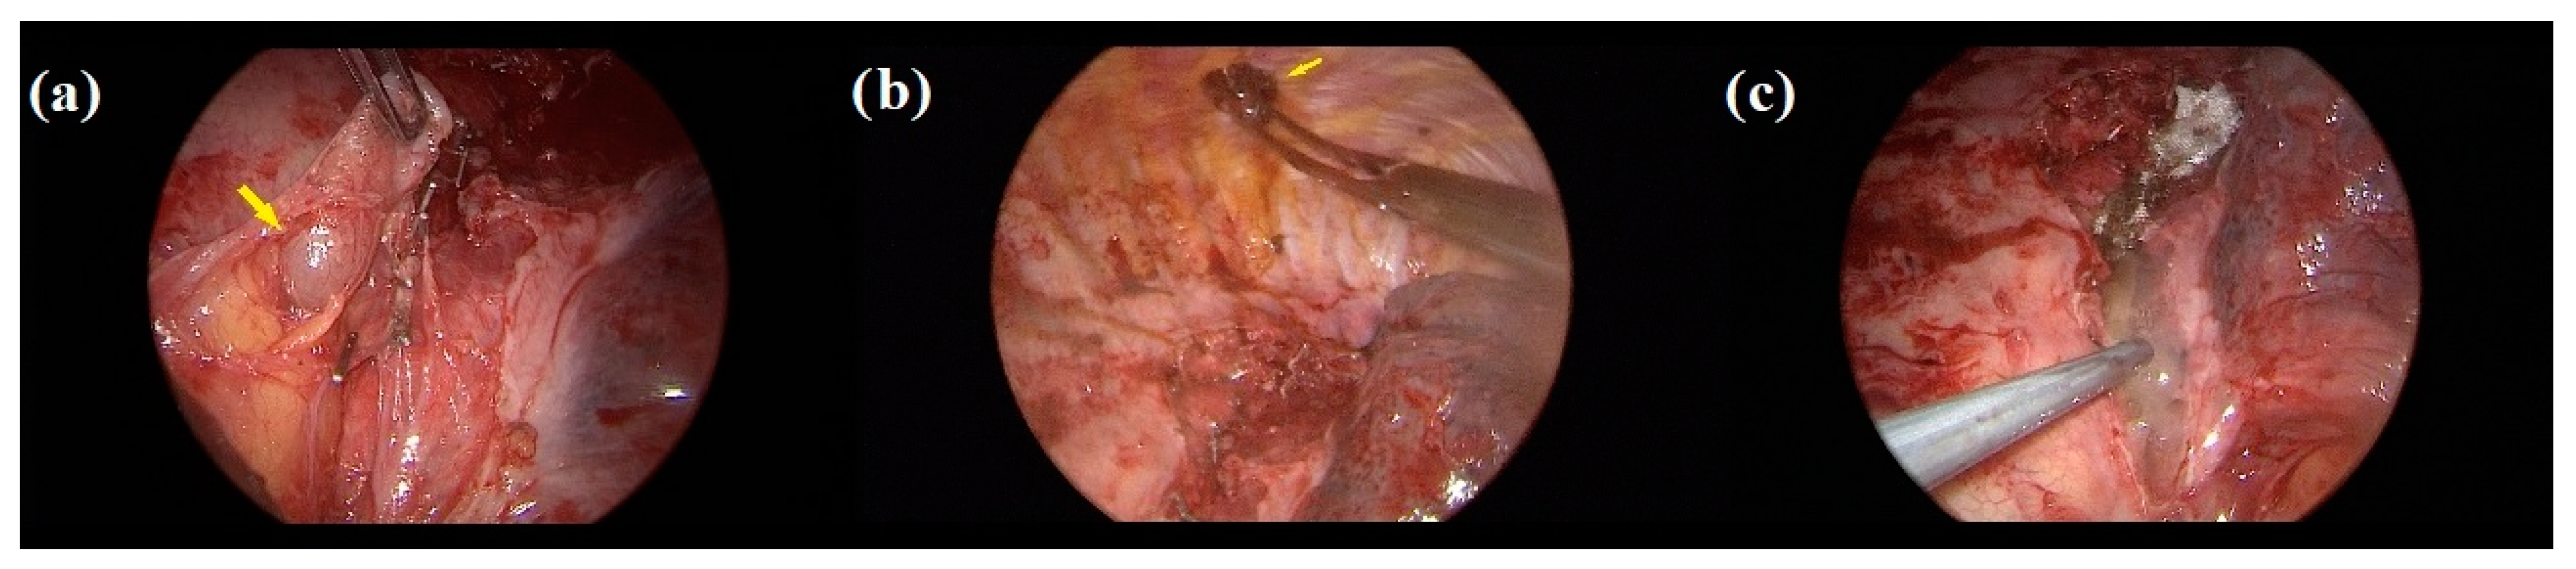

2. Case Presentation